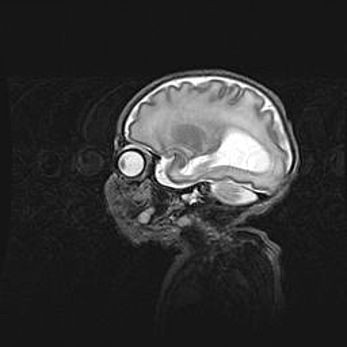

Церебральная ишемия II.

Возраст: 5 дней

Вес: 3400 г

Пол: женский

Окружность головы: 35 см

Срок гестации: 39 недель

Церебральная ишемия – это заболевание, характеризующееся недостаточностью (гипоксией) либо полным прекращением (аноксией) снабжения мозга кислородом по причине закупорки одного или нескольких сосудов. Это приводит к  что метаболическим расстройствам различной степени тяжести в тканях головного мозга, развитию коагуляционных некрозов и гибели нейронов.